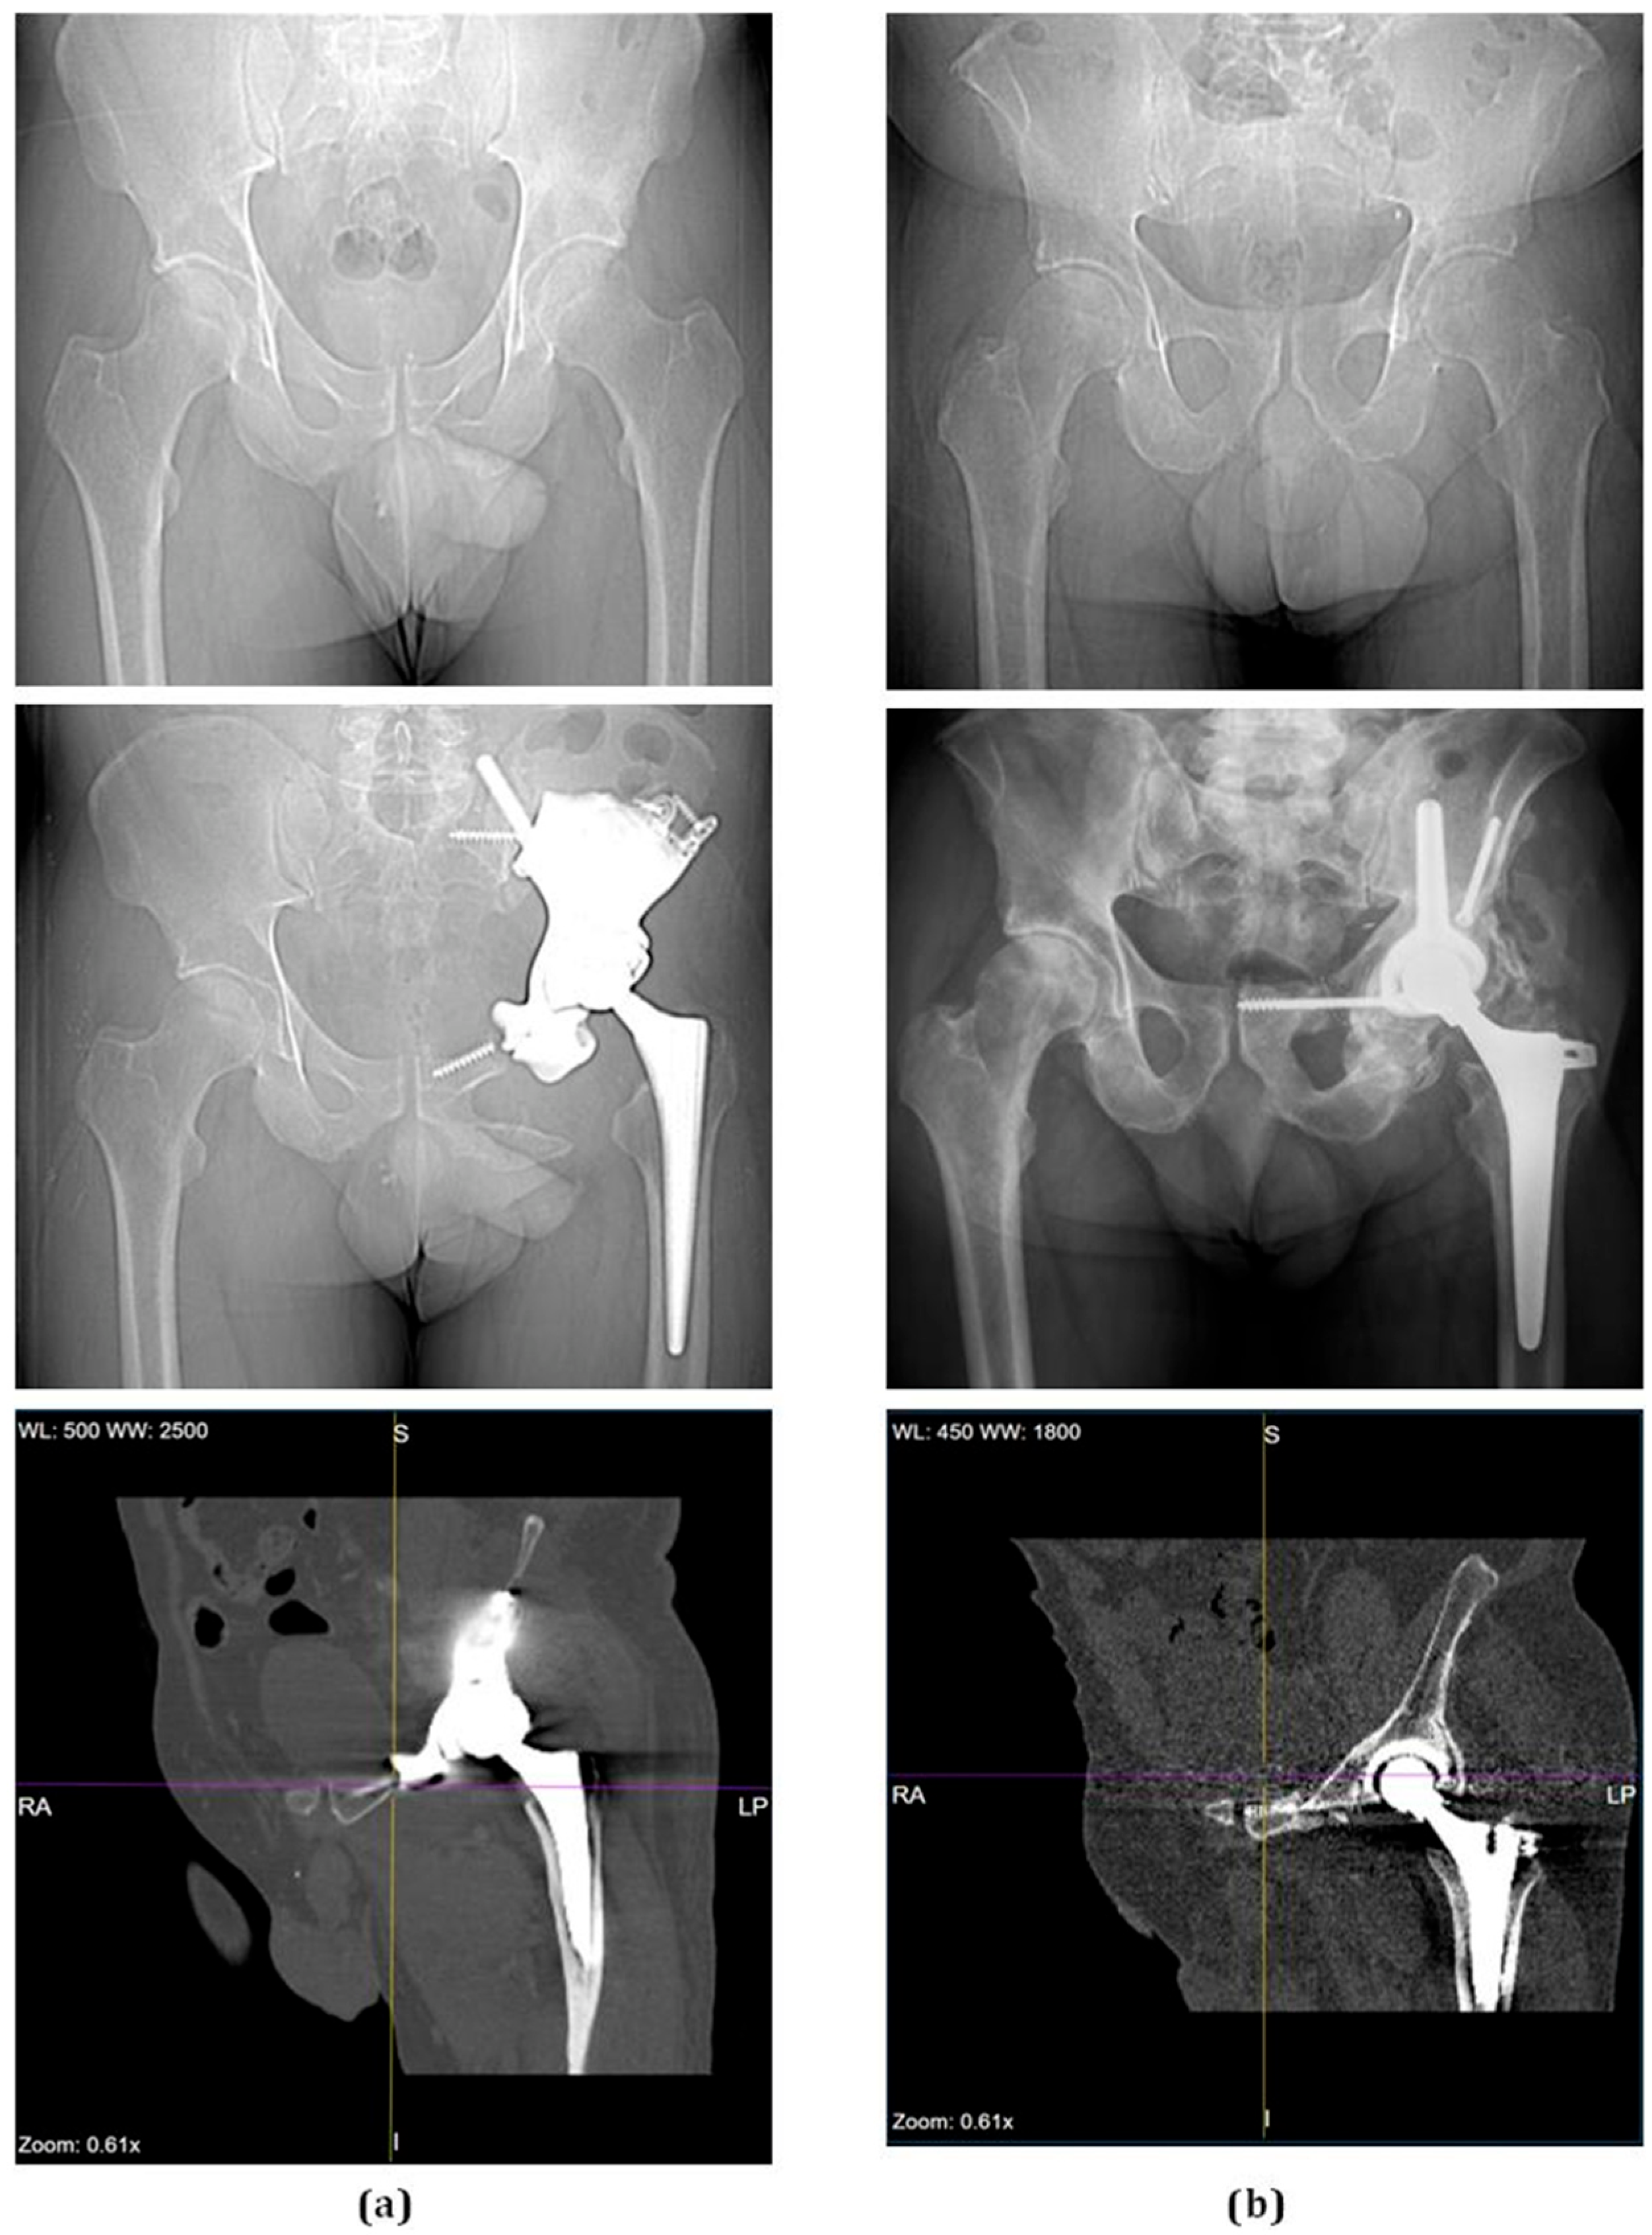

Patients then underwent another CT scan at their 6 month follow-up (Figure 2). Those scans, stored in the form of Digital Imaging and Communications in Medicine files, were segmented using Mimics Innovation Suite (Materialise NV, Leuven, Belgium) to form the 3D anatomical models. No inflammatory reactions or other side effects were observed in this follow-up period after surgery.

Figure 2. Radiological examination of two representative patients, one selected for a 3D-printed custom implant (a) and one for the bone graft implant (b). Pre-operative frontal radiograph (top images), post-operative frontal radiograph at 6 month follow-up (middle images), and CT scan (bottom images). Notice how the CT in (a) has a larger area of high signal intensity in the pelvis, which represents the massive pelvic implant compared to the CT in (b) with a smaller area of signal intensity representing the acetabular cup and bone graft in the pelvis.